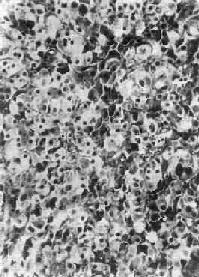

肾上腺皮质腺与局灶性结节性增生的病变相似,两者可以并发。腺通常是单侧单发性,并有薄层包膜,对周围组织有压迫现象,为鉴别的主要点。大小直径为1~5cm,切面黄色,有时呈红褐色,镜下多为类似束状带的泡沫状透明细胞,含有丰富类脂质,有时由类脂含量少的嗜酸性细胞构成,或者两种细胞混合存在。细胞排列成团,由含有毛细血管的少量间质分隔(图15-16)。部分腺为功能性,可引起醛固酮增多症或Cushing综合征,在形态上与非功能性腺没有区别。

图15-16 肾上腺皮质腺

上图 下图